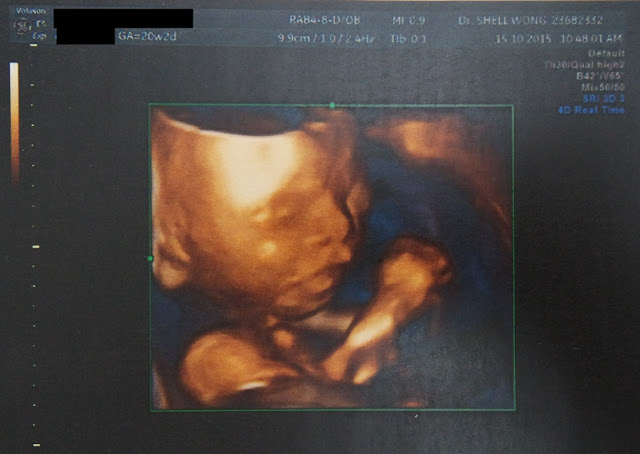

Pregnant with Monster #2 | 27 Weeks Already!

Mentioned here (this blog!) and there on Instagram/Snapchat (both: jacqlibra), I've been pregnant for quite some time.  In fact, I am closer to delivery than baby's conception now - kind of amazed by how swift it progressed!

Baby #2 is expected in 2nd March, which will be in the year of the Monkey, hence for convenience sake, let's call him that for the time now.  We (I) have basically decided on his first name, but not his middle name and Chinese name.  #feelingchallenged